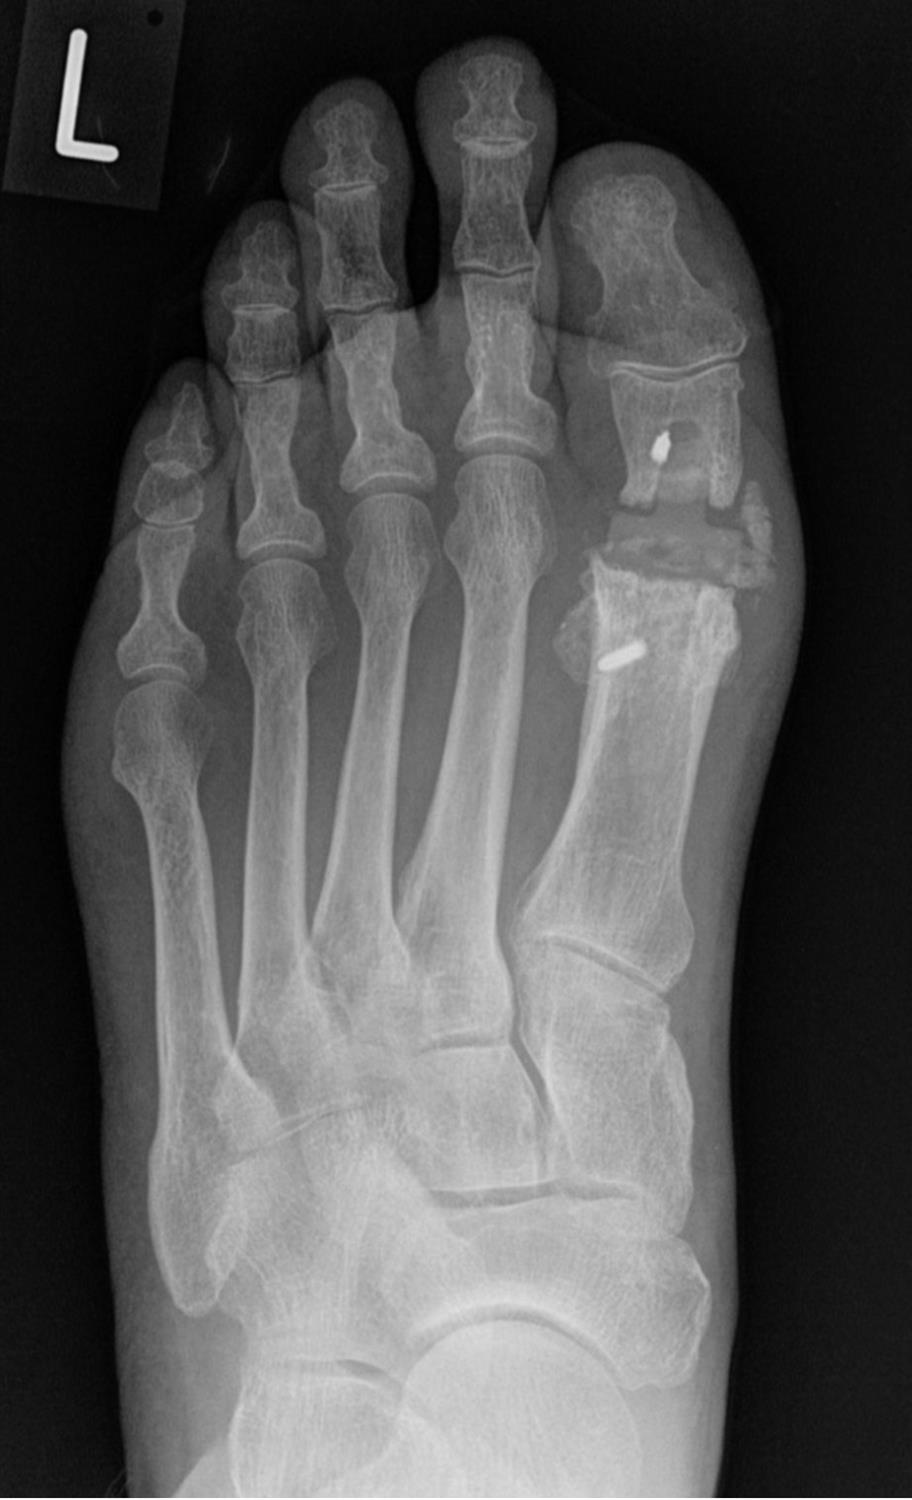

Foot Joints Mtp . Symptoms and signs include pain with walking and tenderness. Pain in the metatarsophalangeal joint is a common musculoskeletal condition which is usually observed when. In other words, metatarsophalangeal joints connect your toe bones to your foot bones. Hallux rigidus is a common foot condition characterized by pain and loss of motion of the 1st mtp joint in adults due to degenerative. Metatarsophalangeal joint pain usually results from tissue changes due to aberrant foot biomechanics. What causes metatarsophalangeal (mtp) joint pain? Metatarsophalangeal joint (articulationes metatarsophalangeale) the. The metatarsophalangeal joints (mtpj) are the articulations in the forefoot between the heads of the metatarsals and the proximal. These joints are surrounded by a thin joint capsule and have ligaments that support them. Between the heads of the metatarsal bones and the bottoms of the proximal phalanges (your toe bones) are the metatarsophalangeal joints.

The metatarsophalangeal joints (mtpj) are the articulations in the forefoot between the heads of the metatarsals and the proximal. Between the heads of the metatarsal bones and the bottoms of the proximal phalanges (your toe bones) are the metatarsophalangeal joints. Metatarsophalangeal joint (articulationes metatarsophalangeale) the. Symptoms and signs include pain with walking and tenderness. What causes metatarsophalangeal (mtp) joint pain? In other words, metatarsophalangeal joints connect your toe bones to your foot bones. Pain in the metatarsophalangeal joint is a common musculoskeletal condition which is usually observed when. Metatarsophalangeal joint pain usually results from tissue changes due to aberrant foot biomechanics. These joints are surrounded by a thin joint capsule and have ligaments that support them. Hallux rigidus is a common foot condition characterized by pain and loss of motion of the 1st mtp joint in adults due to degenerative.

Foot Joints Mtp Pain in the metatarsophalangeal joint is a common musculoskeletal condition which is usually observed when. Metatarsophalangeal joint (articulationes metatarsophalangeale) the. What causes metatarsophalangeal (mtp) joint pain? Between the heads of the metatarsal bones and the bottoms of the proximal phalanges (your toe bones) are the metatarsophalangeal joints. Symptoms and signs include pain with walking and tenderness. Hallux rigidus is a common foot condition characterized by pain and loss of motion of the 1st mtp joint in adults due to degenerative. Metatarsophalangeal joint pain usually results from tissue changes due to aberrant foot biomechanics. The metatarsophalangeal joints (mtpj) are the articulations in the forefoot between the heads of the metatarsals and the proximal. These joints are surrounded by a thin joint capsule and have ligaments that support them. Pain in the metatarsophalangeal joint is a common musculoskeletal condition which is usually observed when. In other words, metatarsophalangeal joints connect your toe bones to your foot bones.